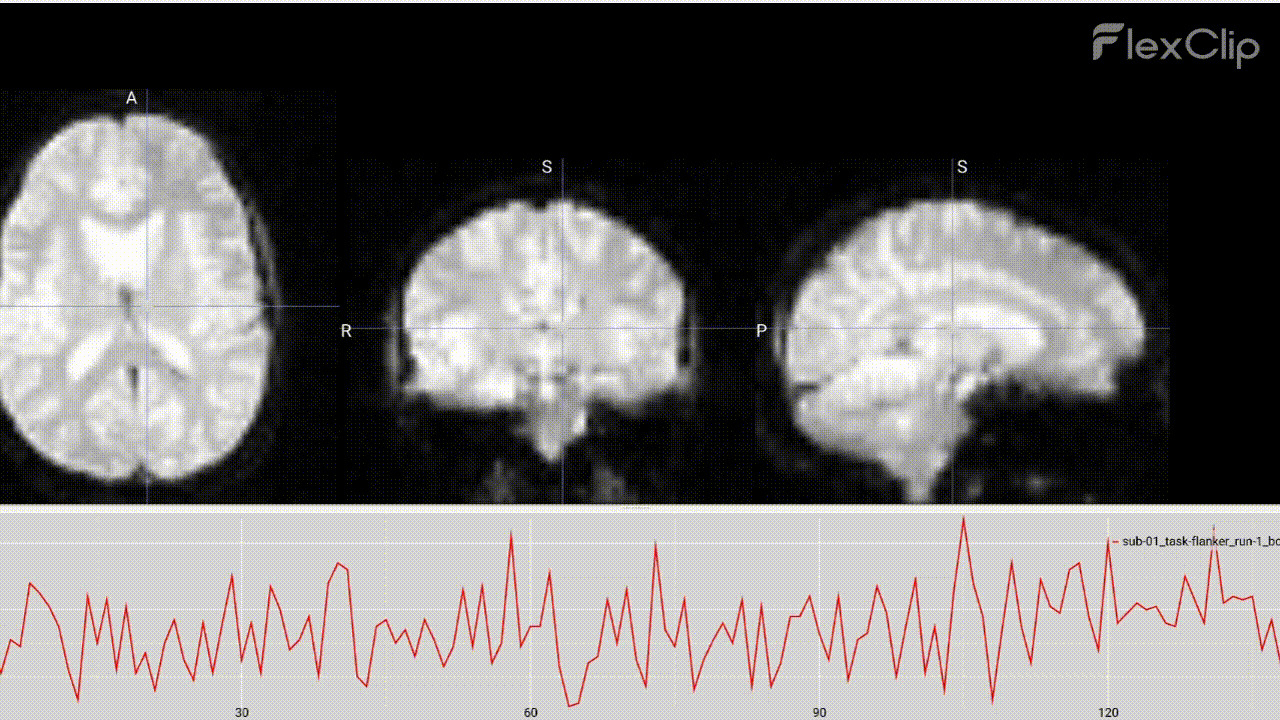

Time Series:

Each time series represents the intensity of the BOLD signal of every ROI (Region of Interest) along the rs-fRMI.